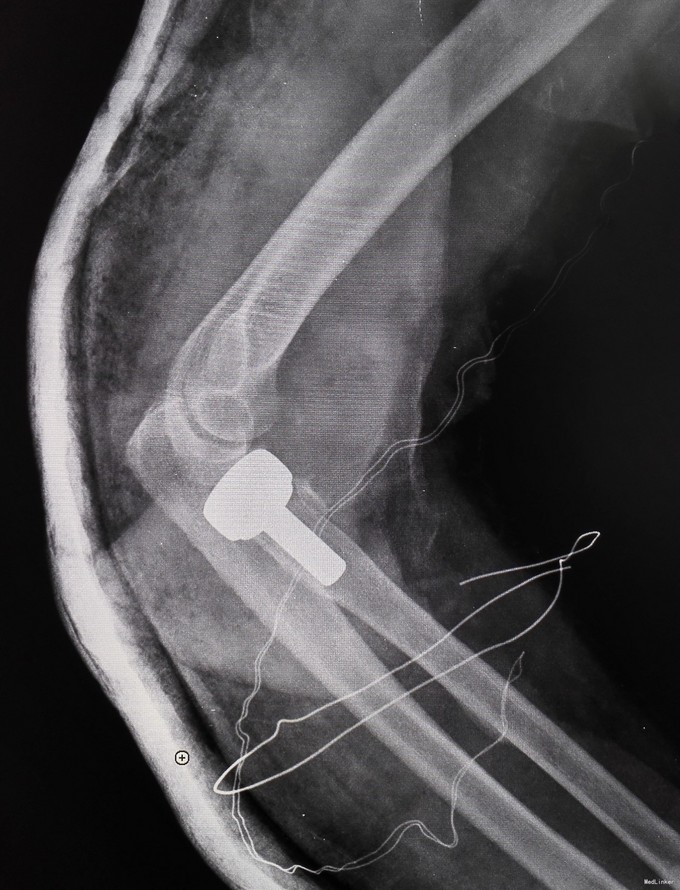

诊断为肘关节恐怖三联征(肘关节后脱位伴桡骨头和尺骨冠状突骨折),消肿后予以切开复位Wright桡骨小头假体置换,外侧副韧带修补,冠状突骨块小,未行固定。

术后近两年,桡骨近端假体承载处骨赘增生,但患者功能良好,无不适主诉,疗效满意